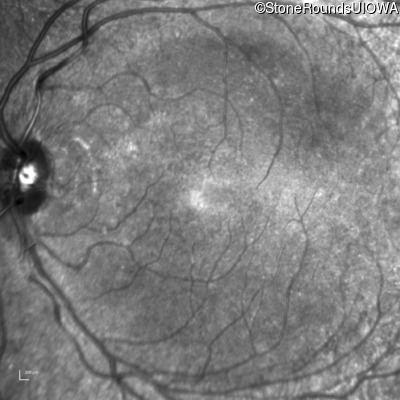

Infrared Fundus Photograph - Left - 20/25

Exemplar